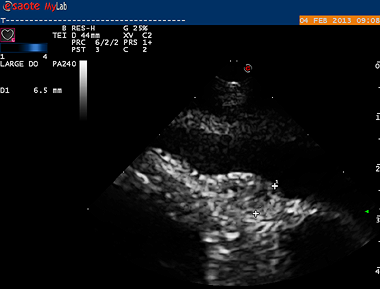

Small 6mm suspicious area at the level of the junction between the right atrium and right ventricle

The first patient to benefit from the new My Lab Class C was an 11-year-old, female German shepherd dog with suspected cardiac neoplasia following several episodes of haemorrhage into the pericardium. A normal echocardiographic examination identified a small suspect area but it was in a part of the heart that was very difficult to approach surgically.

However, a trans-oesophageal examination revealed that another small mass close to the tip of the right auricle was actually the origin of the bleeding. The dog underwent surgery to remove the mass and subsequently made a full recovery. Without the My Lab Class C there would have been no viable options for this dog.